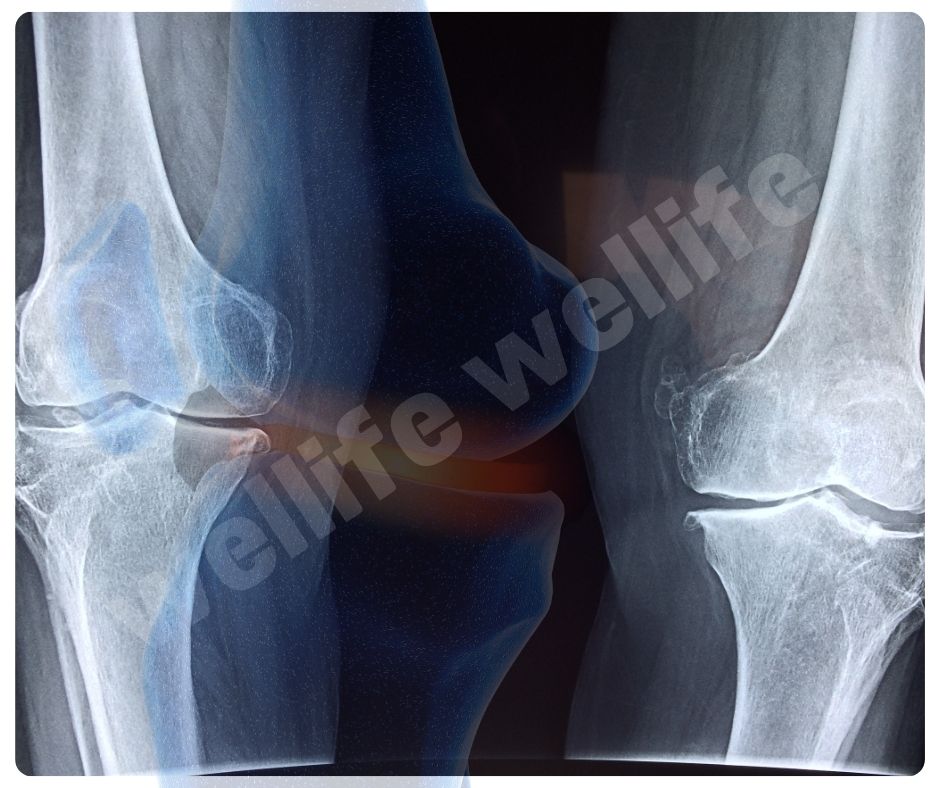

최근 연구에 따르면 글루코사민은 연골 세포의 생성을 촉진하고, 연골 조직의 회복을 돕는 효과가 있습니다. 2023년에 발표된 한 연구에서는 글루코사민이 연골 세포의 대사 활동을 증가시키고, 연골 조직의 손상을 줄이는 데 효과적이라는 결과를 보여주었습니다.

글루코사민의 항염증 효과에 대한 연구도 활발히 진행되고 있습니다. 2022년에 발표된 한 연구에서는 글루코사민이 염증 매개체인 사이토카인의 생성을 억제하여 염증 반응을 줄이는 데 도움이 된다는 결과를 발표했습니다 (UVM College of Medicine). 이는 관절염 환자의 통증과 염증을 효과적으로 줄이는 데 중요한 역할을 합니다.

장기간 글루코사민을 복용하는 것이 안전한지에 대한 연구도 있습니다. 2021년에 발표된 장기 연구에서는 글루코사민을 5년 이상 복용한 환자들에서 심각한 부작용이 나타나지 않았으며, 오히려 관절 건강이 지속적으로 개선되는 결과를 보여주었습니다.